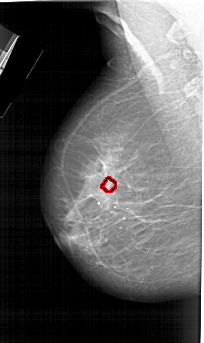

A_1728_1.RIGHT_CC

RIGHT_CC LINES 6856 PIXELS_PER_LINE 3841 BITS_PER_PIXEL 12 RESOLUTION 43.5 NON_OVERLAY

FILE: A_1728_1.LEFT_CC.OVERLAY

TOTAL_ABNORMALITIES 1

ABNORMALITY 1

LESION_TYPE CALCIFICATION TYPE PLEOMORPHIC DISTRIBUTION CLUSTERED

ASSESSMENT 4

SUBTLETY 2

PATHOLOGY MALIGNANT

TOTAL_OUTLINES 1

BOUNDARY